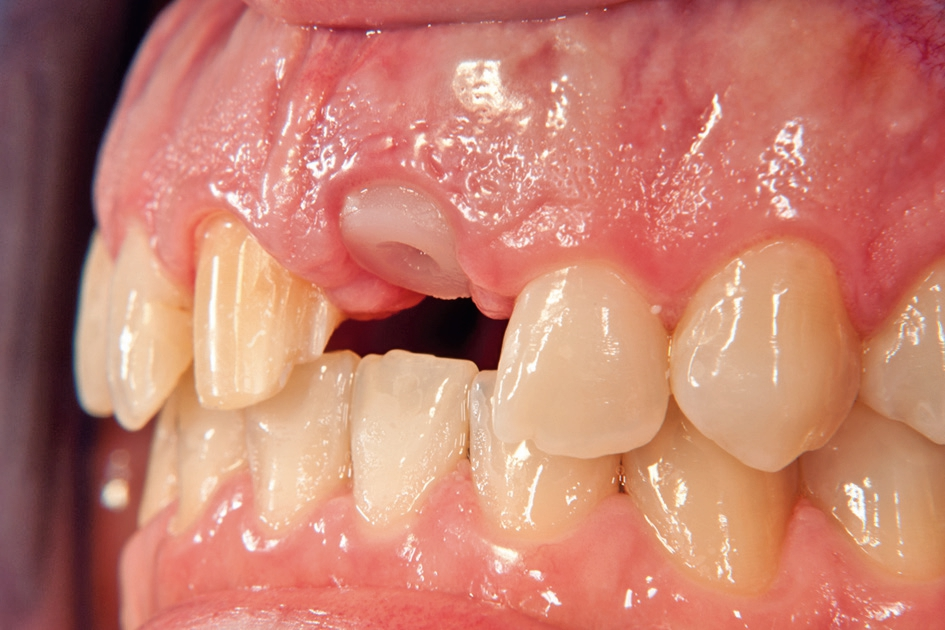

Gleichzeitig mit der prothetischen Versorgung des Implantats wurde auch für Zahn 11 ein Veneer geplant. Zum Einsatz kam ein Zeramex T Implantat Durchmesser 5,5 mm, Länge 12 mm. Für die Kronenversorgung wurde ein mit e. Max überpresstes CAD-Abutment gewählt. Während der Einheilphase des Implantats kam eine Sunflex-Prothese zum Einsatz.